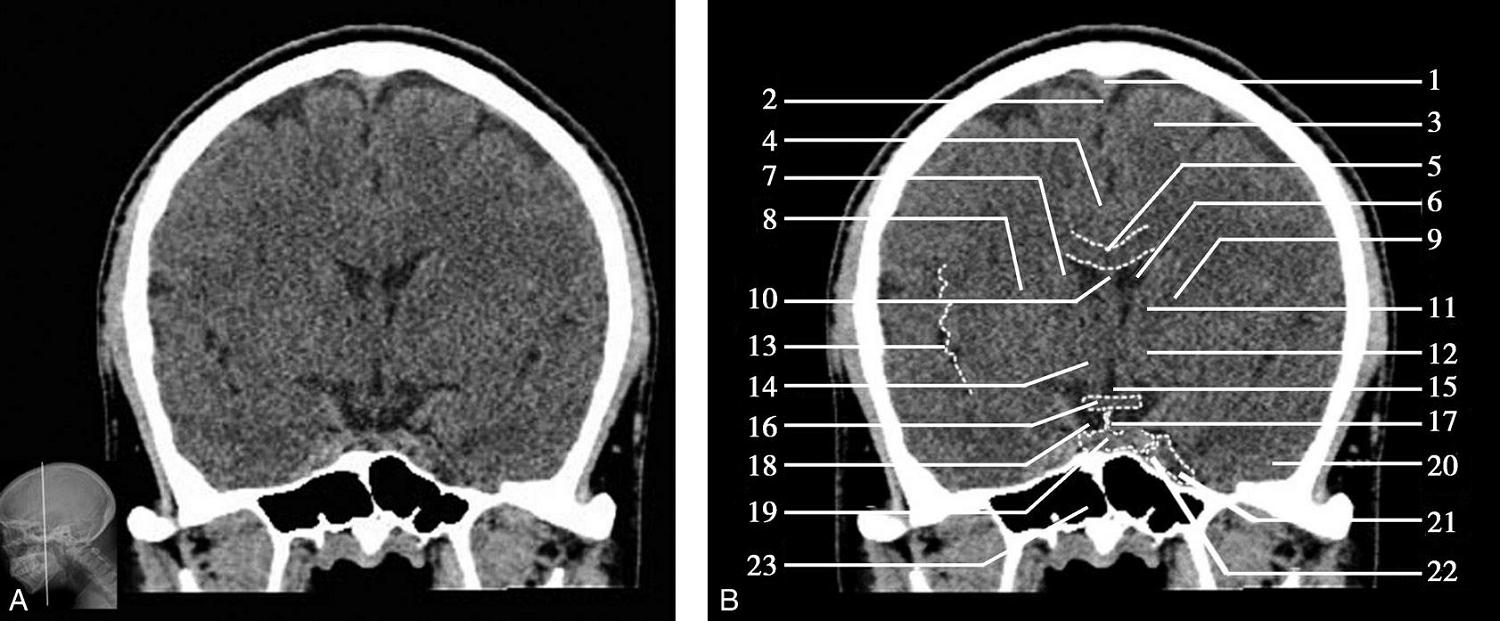

重要结构:卵圆孔、棘孔、破裂孔、斜坡、颞骨岩部、颈静脉孔(图1-2-1、图1-2-2)。

图1-2-1 颅底层面

A.横断面;B.横断面标注

1.晶状体;2.筛窦;3.颞肌;4.中颅窝底;5.外耳道;6.延髓;7.乙状窦;8.小脑半球;9.眼球;10.眼眶;11.上颌窦;12.蝶窦;13.乳突;14.耳郭;15.小脑蚓部;16.枕内隆凸

图1-2-2 颅底层面(骨窗)

1.鼻骨;2.筛窦纸板;3.颧骨眶突;4.翼腭窝;5.蝶骨大翼;6.卵圆孔;7.破裂孔;8.颞骨颧突;9.棘孔;10.斜坡;11.颞骨岩部;12.乳突;13.颈静脉孔;14.枕乳突缝;15.枕骨;16.枕内隆凸

层面前部呈开口向前的“V”字形,正中为鼻中隔,向两侧依次为筛窦和眼眶,眼眶内前部为眼球,后部为眶脂体。翼腭窝位于眼眶后部,窝内含有脂肪并有上颌神经通过。层面中部为蝶骨体,蝶骨体中部可见含气蝶窦,蝶窦后方为枕骨基底部,两者呈前后关系,其上面构成斜坡。蝶窦两侧为蝶骨大翼,其后外侧缘处由前向后可见卵圆孔和棘孔,分别有下颌神经和脑膜中动脉通过。斜坡外侧、岩骨尖前方为破裂孔。蝶骨大翼与眶外侧壁的颧骨借颧弓相连,颧弓和蝶骨大翼之间有咬肌及颞肌。层面中部外侧为外耳道。颞骨岩部呈“八”字形,相互之间借破裂孔软骨、蝶岩软骨结合和岩枕软骨结合连接。岩部后外侧的乳突部内可见乳突小房,乳突部与枕骨相接。岩骨后部可见颈静脉孔,内有颈内静脉、舌咽神经、迷走神经和副神经通过。层面后部为颅后窝,其内可见延髓,延髓前方为延髓前池,内有椎动脉,后外侧为小脑半球下部,后方为第四脑室、小脑扁桃体及小脑蚓部。